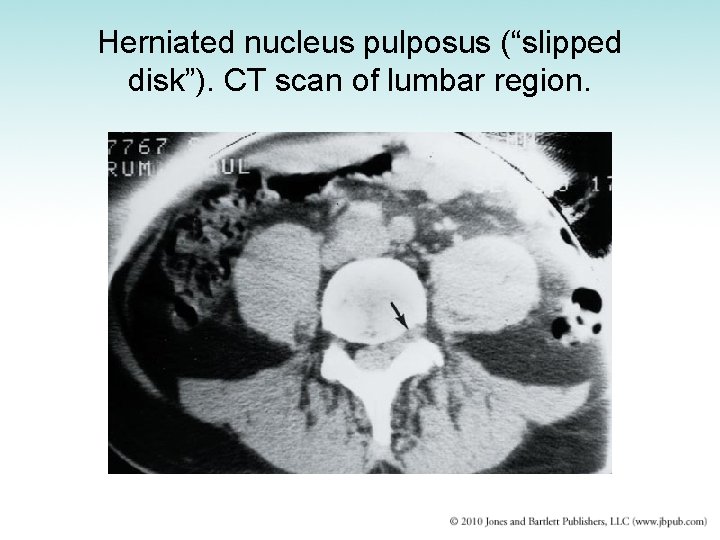

Intervertebral Disk Disease • Intervertebral disks undergo progressive wear -and-tear degeneration of both nucleus and annulus • Nucleus pulposus may be extruded through tear in annulus fibrosus • Manifestation – Sudden onset of back pain radiating down the leg • Diagnosis: CT scan or myelogram • Treatment: surgery

Herniated nucleus pulposus (“slipped disk”). CT scan of lumbar region.